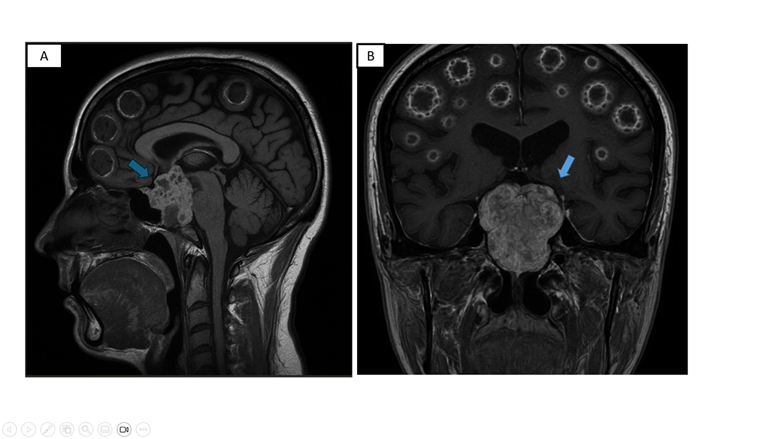

En la resonancia magnética (RMN) craneal se evidenció: adenohipófisis de 8x5x14 mm con reforzamiento heterogéneo posterior al contraste; engrosamiento heterogéneo de la silla turca y región petroclival con extensión a las regiones paraselares sugerente de macroadenoma hipofisiario. A nivel de calota, presencia de múltiples imágenes iso-hiperintensas en T1 y T2 que se refuerzan con el contraste de forma periférica y heterogénea, a considerar lesiones en sacabocado. (figura 1)

Figura 1: RMN craneal T1 sagital (A) y coronal (B): Adenohipófisis de 8x5x14 mm con reforzamiento heterogéneo posterior al contraste; engrosamiento heterogéneo de la silla turca y región petroclival con extensión a las regiones paraselares (flecha)